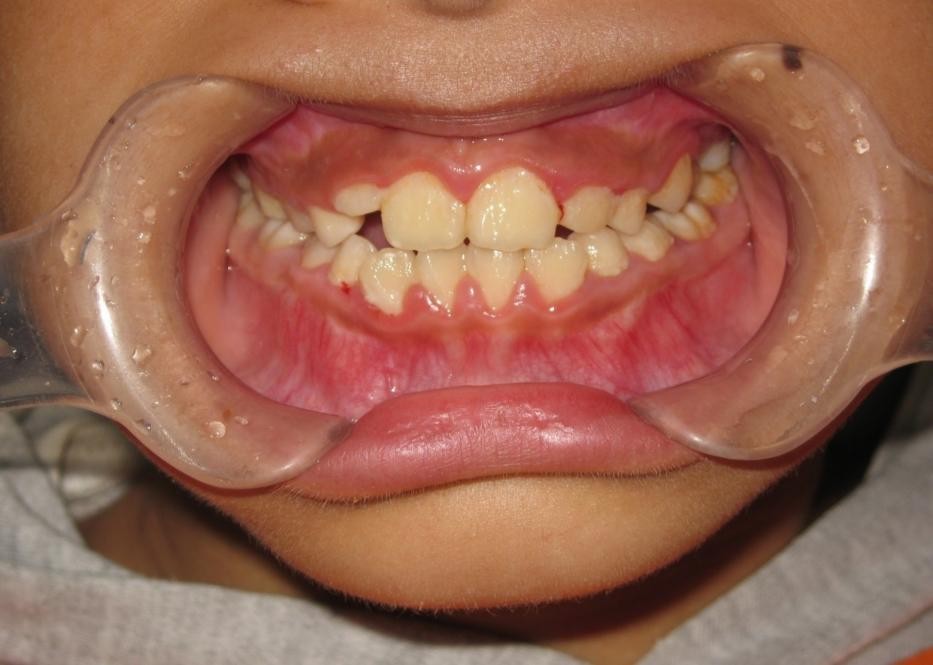

2.前牙反合(兜齿)

(图为反合矫治前后对比)

下图为早期矫治前后面型和口内像对比,可以看到矫治后的患儿面型左右基本对称,下牙列的偏斜程度也明显改善,前牙的反合得到解除,去除了上颌骨发育的不利因素。接下来就是等待患儿换完牙以后进行二期治疗,二期治疗可以从三维方向上控制牙齿的移动方向,进一步平衡咬合,使得矫治效果更加稳定。二期治疗的矫治器可以选择固定矫治器也可以选择无托槽隐形矫治器。